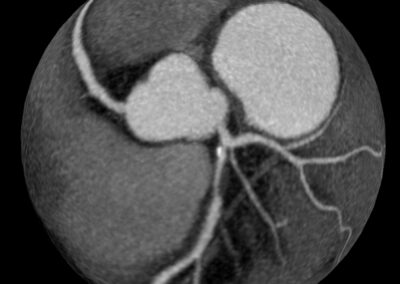

Τρισδιάστατη και δισδιάστατη απεικόνιση των στεφανιαίων αγγείων όπου διακρίνεται σημαντική στένωση λίγο μετά την έκφυσή του πρόσθιου κατιόντα κλάδου